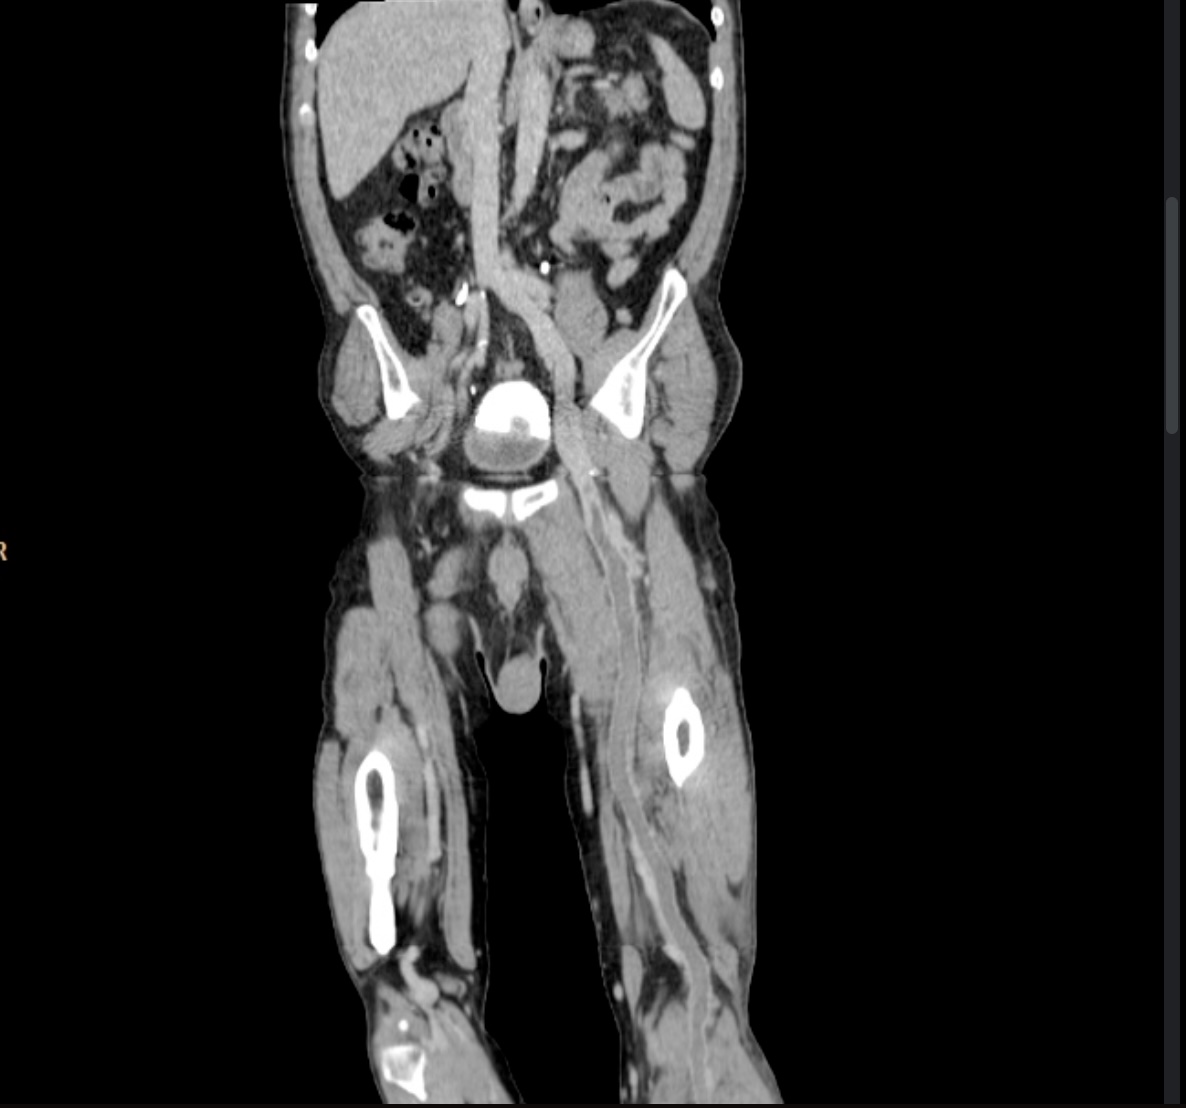

• CT venography

• CT scan with contrast dye to visualize venous thrombus

• 90% sensitive, 95% specific

• useful when pulmonary embolism is suspected or following an inconclusive ultrasound study

• CT (90% sensitive, 95% specific)